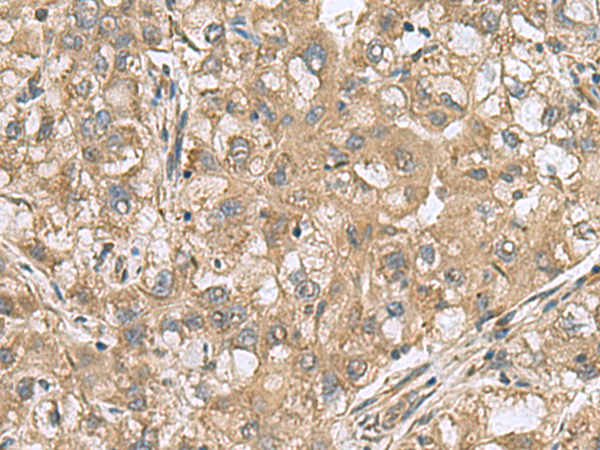

分类: 科研抗体货号: P10216别名: SFRSK2应用: IHC反应种属: Human, Mouse